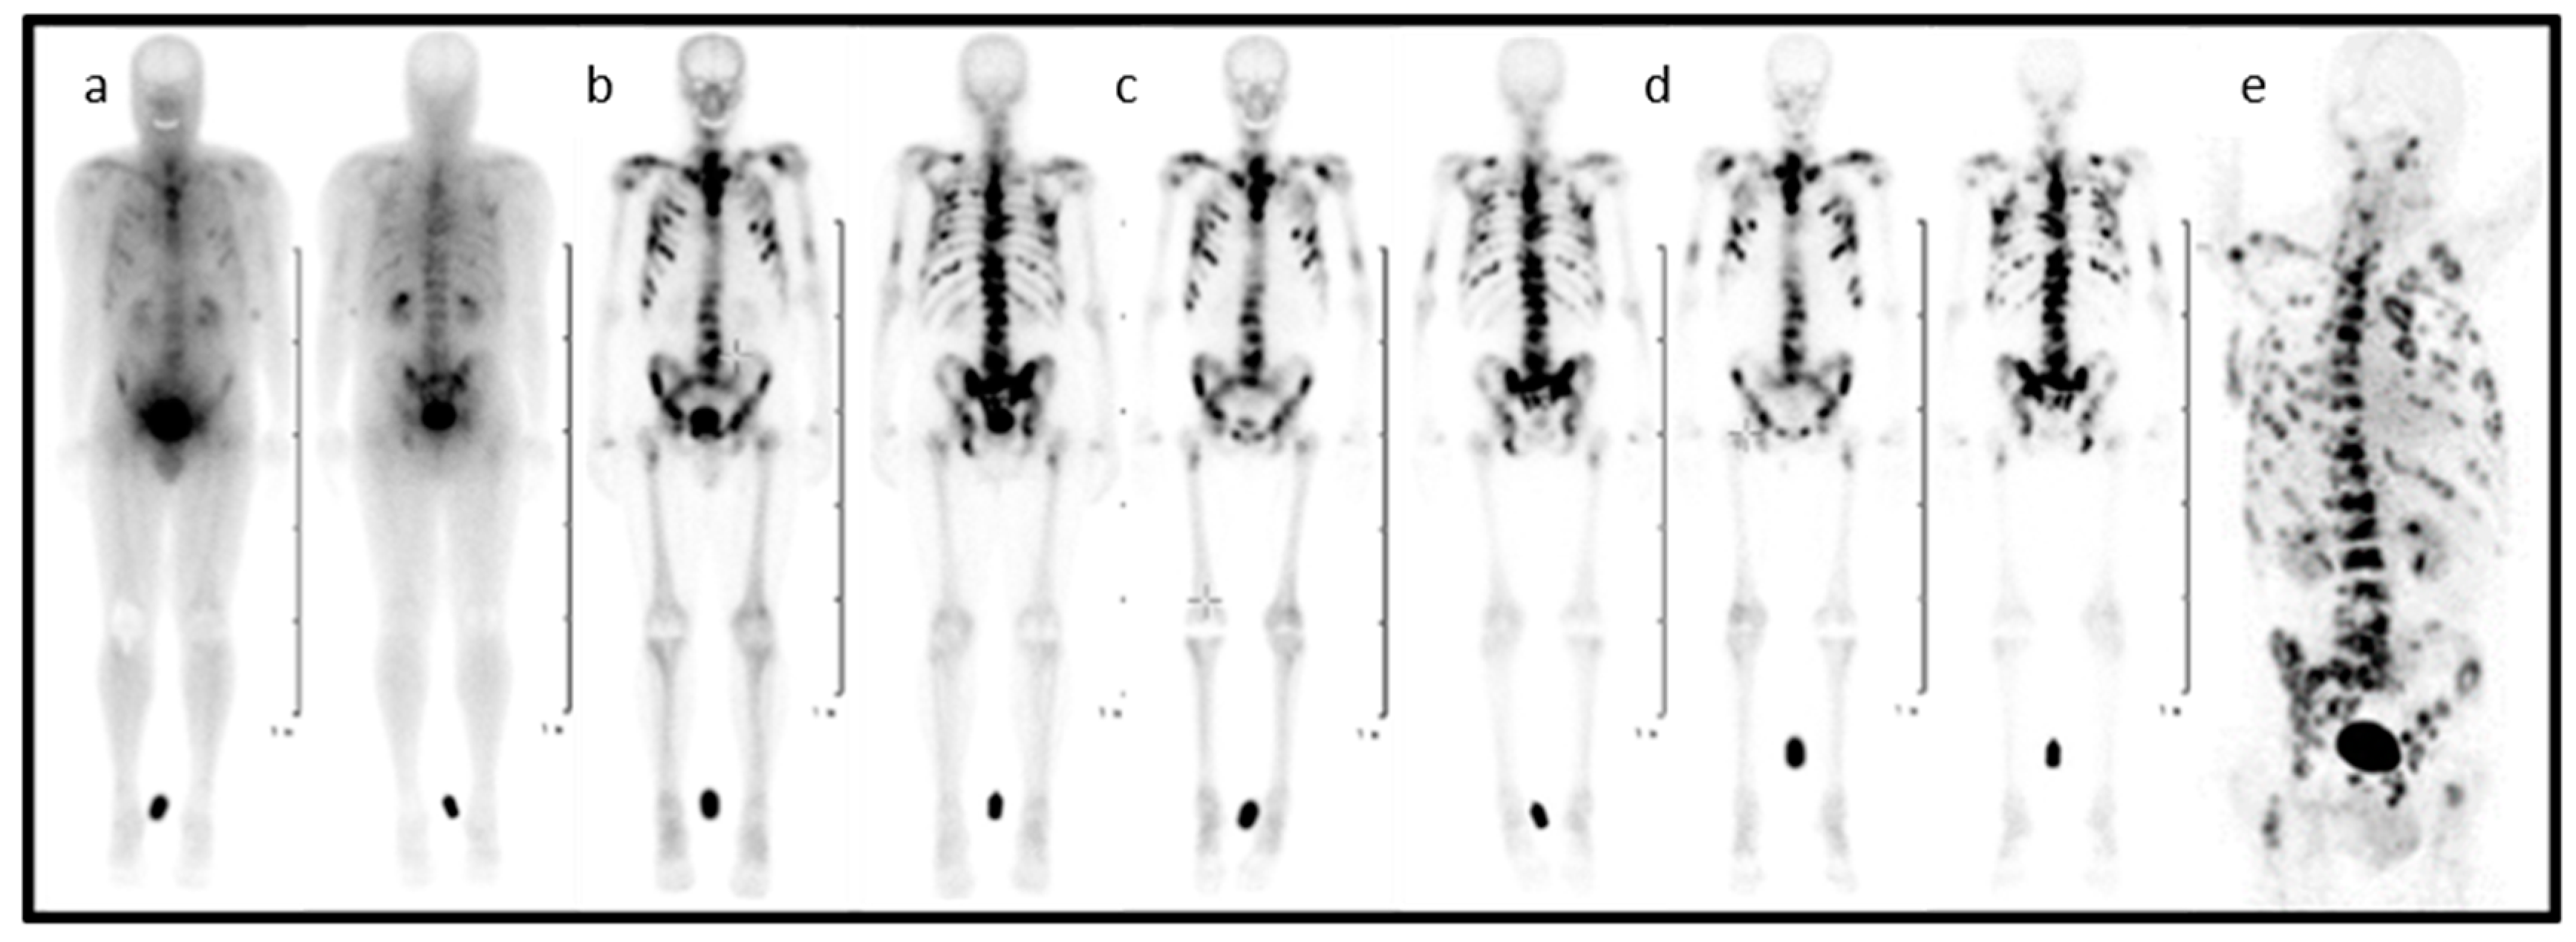

Figure 2. Planar scintigraphy (anterior and posterior) of [177Lu]Lu-DOTA-ZOL at different time points (ad) and PET/CT of gallium-68 [68Ga]Ga-DOTA-ZOL (e) in a bronchial carcinoma patient with secondary bone metastases [41].

In the entire process, from diagnosis to the treatment of patients suffering from skeletal metastatic disease, the techniques of nuclear medicine play a key role. 99mTc-labelled bisphosphonates such as methylene diphosphate (MDP) or hydroxy methylene diphosphate (HMDP) have been used in the clinical diagnosis of metastatic bone cancer for many years [31], and therapeutic radionuclides have proven their value in bone pain palliation [32,33,34]. From the current generation of bisphosphonates, zoledronate’s high affinity for hydroxyapatite and its high antiresorptive potency makes it particularly interesting as a targeting vector for theragnostic applications in nuclear medicine. One of the first bisphosphonate derivates suitable for diagnostic imaging as well as therapeutic treatment was (4-{[(bis(phosphonomethyl))carbamoyl]methyl}-7,10-bis(carboxymethyl)-1,4,7,10-tetraazacyclododec-1-yl) acetic acid (BPAMD) [35,36]. BPAMD combines the bisphosphonate with a chelator, namely 1,4,7,10-tetraazacyclododecane-1,4,7,10-tetraacetic acid (DOTA). DOTA forms stable complexes with a variety of medicinal applied radiometals, thus enabling the use of the entire spectrum of nuclear medicine techniques. The first patient studies with gallium-68 68Ga/177Lu-labelled BPAMD proved the potential of this theragnostic approach of a DOTA-conjugated bisphosphonate [37,38,39]. This proof-of-principle paved the way for more sophisticated macrocyclic bisphosphonates, employing more potent bisphosphonate basic structures like pamidronate and zoledronate [40], the latter of which already proved its enhanced potential in diagnosis and therapy Figure 2 [41,42].